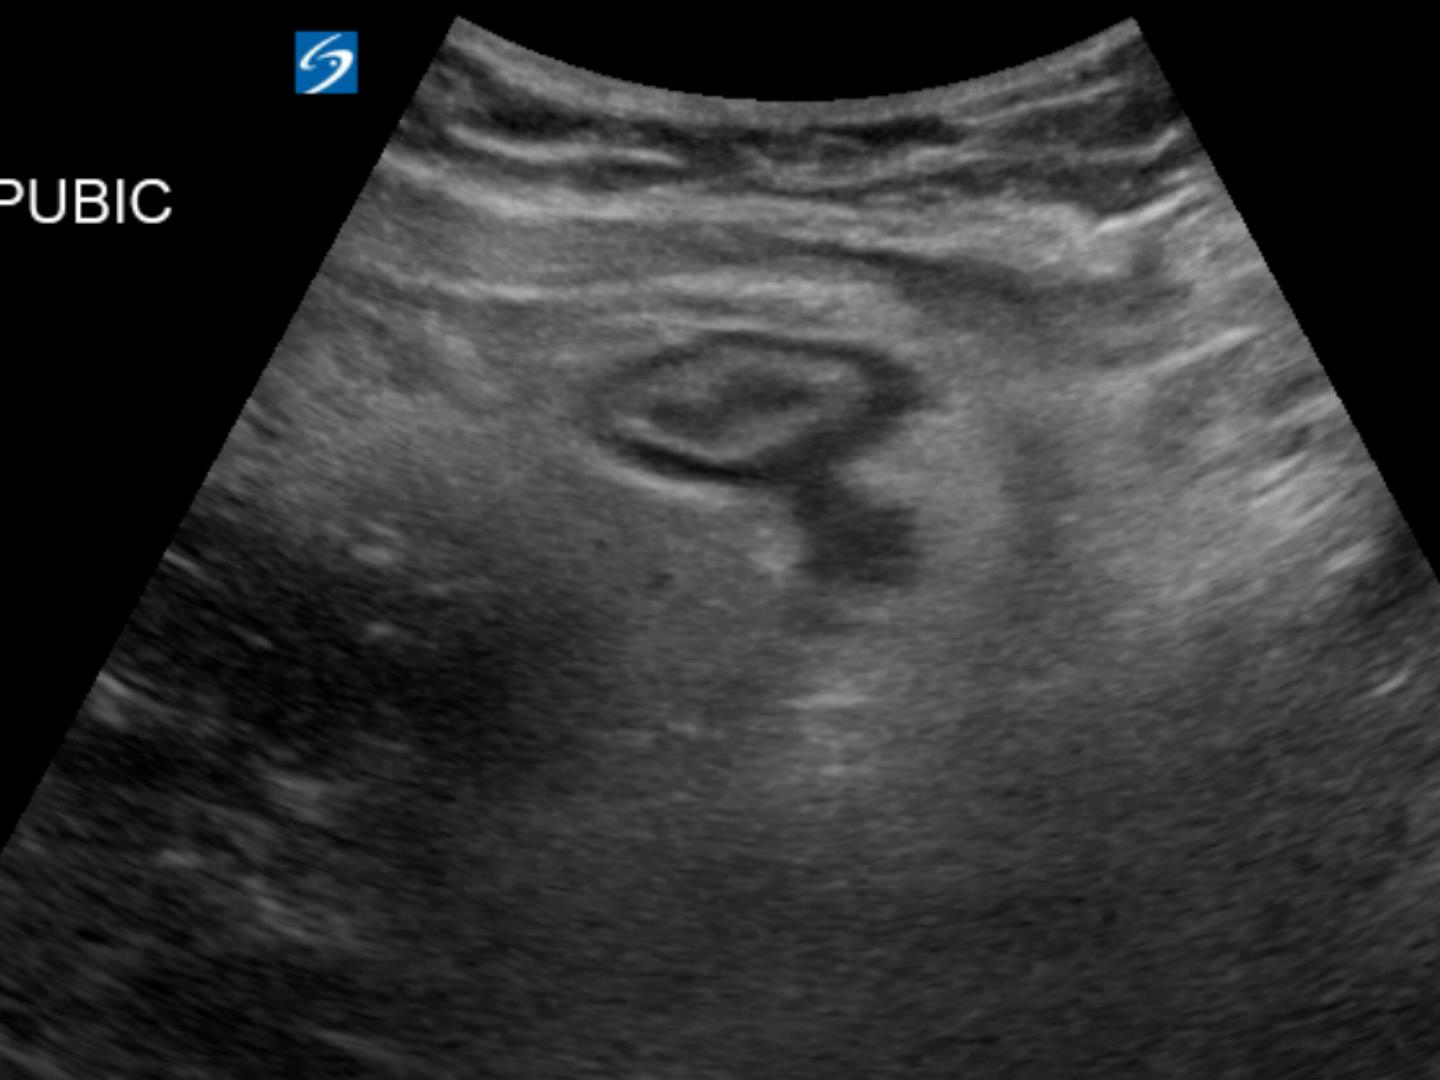

From www.criticalcare-sonography.com

Diverticulitis Critical Care Sonography Diverticulitis Skin Lesions The primary symptom is abdominal pain. Lesions most commonly occur on the trunk and arms, sparing the face, palms and soles. Treatment is with bowel rest, sometimes antibiotics, and occasionally surgery. The most common skin or mucocutaneous lesions associated with ibd are en, pyoderma gangrenosum (pg), and aphthous. Diagnosis is by ct and ultrasound. Symptoms of colonic diverticulitis usually begin. Diverticulitis Skin Lesions.

From sonographie.org

Diverticulitis Atlas of Ultrasound Diverticulitis Skin Lesions The primary symptom is abdominal pain. Diverticulitis is inflammation with or without infection of a diverticulum, which can result in phlegmon of the bowel wall, peritonitis, perforation, fistula, or abscess. Most often, pain is in the. Treatment is with bowel rest, sometimes antibiotics, and occasionally surgery. Symptoms of colonic diverticulitis usually begin in the left iliac fossa with unremitting pain. Diverticulitis Skin Lesions.